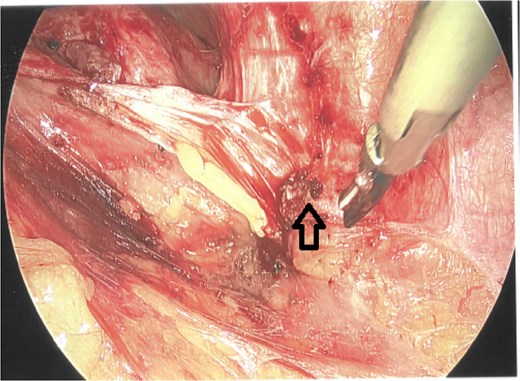

As a result, a laparoscopic left hemicolectomy was performed. The descending colon was medialised by incising the White line of Toldt from the proximal sigmoid colon, with dissection of splenocolic, phrenicocolic and the pancreaticocolic ligaments proximally. The colocutaneous fistula was identified during medialisation of the proximal descending colon and was excised (Fig. 1). There were chronic changes of inflammation and fibrosis around this region, without an abscess cavity. The distal transverse colon was then mobilised by dissecting the gastrocolic ligament to enter the lesser sac. The mobilised colon was then exteriorised through a midline laparotomy, the left colic and the left branch of the middle colic arteries were ligated and an extracorporeal side to side, functional end to end stapled anastomosis occurred using NTLC 75 mm blue reload stapler between the distal transverse and the distal descending colon. Indocyanide Green (ICG) angiography was used to confirm good perfusion at the anastomosis (Fig. 2). A well vascularised omental patch covered the remnant fistula tract on the lateral posterior abdominal wall. Postoperative recovery was uncomplicated. Histopathology was consistent with a fistula tract without evidence of malignancy.

Laparoscopic view of the excised colocutaneous fistula (arrow). The descending colon has been retracted medially.